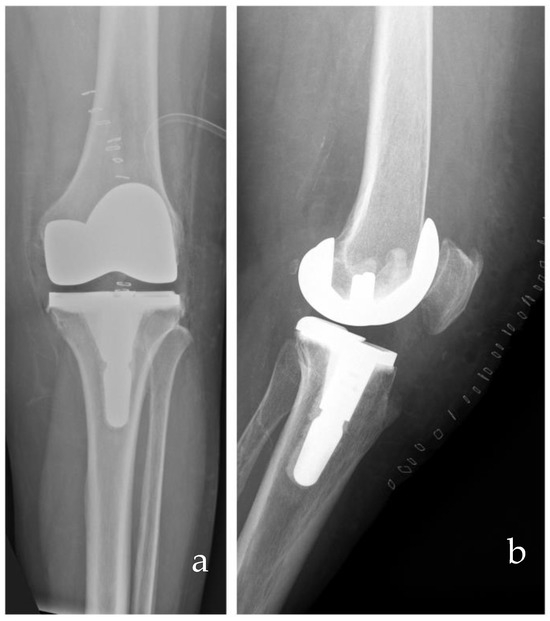

- Rossi, S.M.P.; Benazzo, F. Individualized Alignment and Ligament Balancing Technique with the ROSA® Robotic System for Total Knee Arthroplasty. Int. Orthop. 2023, 47, 755–762. [Google Scholar] [CrossRef] [PubMed]